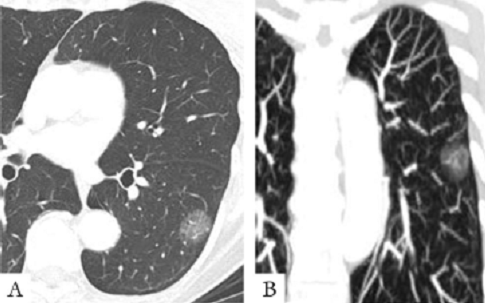

在检查发现的肺部小结节患者中,相当一部分病人是单个的,很小的结节,称为孤立性肺部结节。孤立性肺部结节(solitary pulmonary nodule, SPN)是指肺部单发的、直径<3cm不伴有肺不张和肺门淋巴结肿大的类圆形病灶。在SPN中,良性肉芽肿约占50%,恶性肿瘤约占30%,其次有错构瘤、肺硬化性血管瘤、曲菌球、肺内淋巴结等。一般认为结节直径越小,病灶内显示脂肪和钙化者常提示为良性,其钙化之特点是呈中心性、爆米花状或弥漫分布的同心圆性,而有报告4%~7%的

肺癌也偶见钙化,但往往呈不规则的点状分布;恶性结节常呈分叶、细小短毛刺、空泡征、胸膜凹陷征、肺血管集中征以及病灶明显强化,最能提示为周围型肺癌的征象依次为空泡征、分叶征、短毛刺、胸膜凹陷和血管集束征。尽管良、恶性的CT征象在诊断中具有一定的指导意义,然而这也并非绝对,因为良、恶性病变的表现也有互相的交叉和重叠,而仅根据影像学对良、恶性肺部病变鉴别的正确率约为70%~80%。